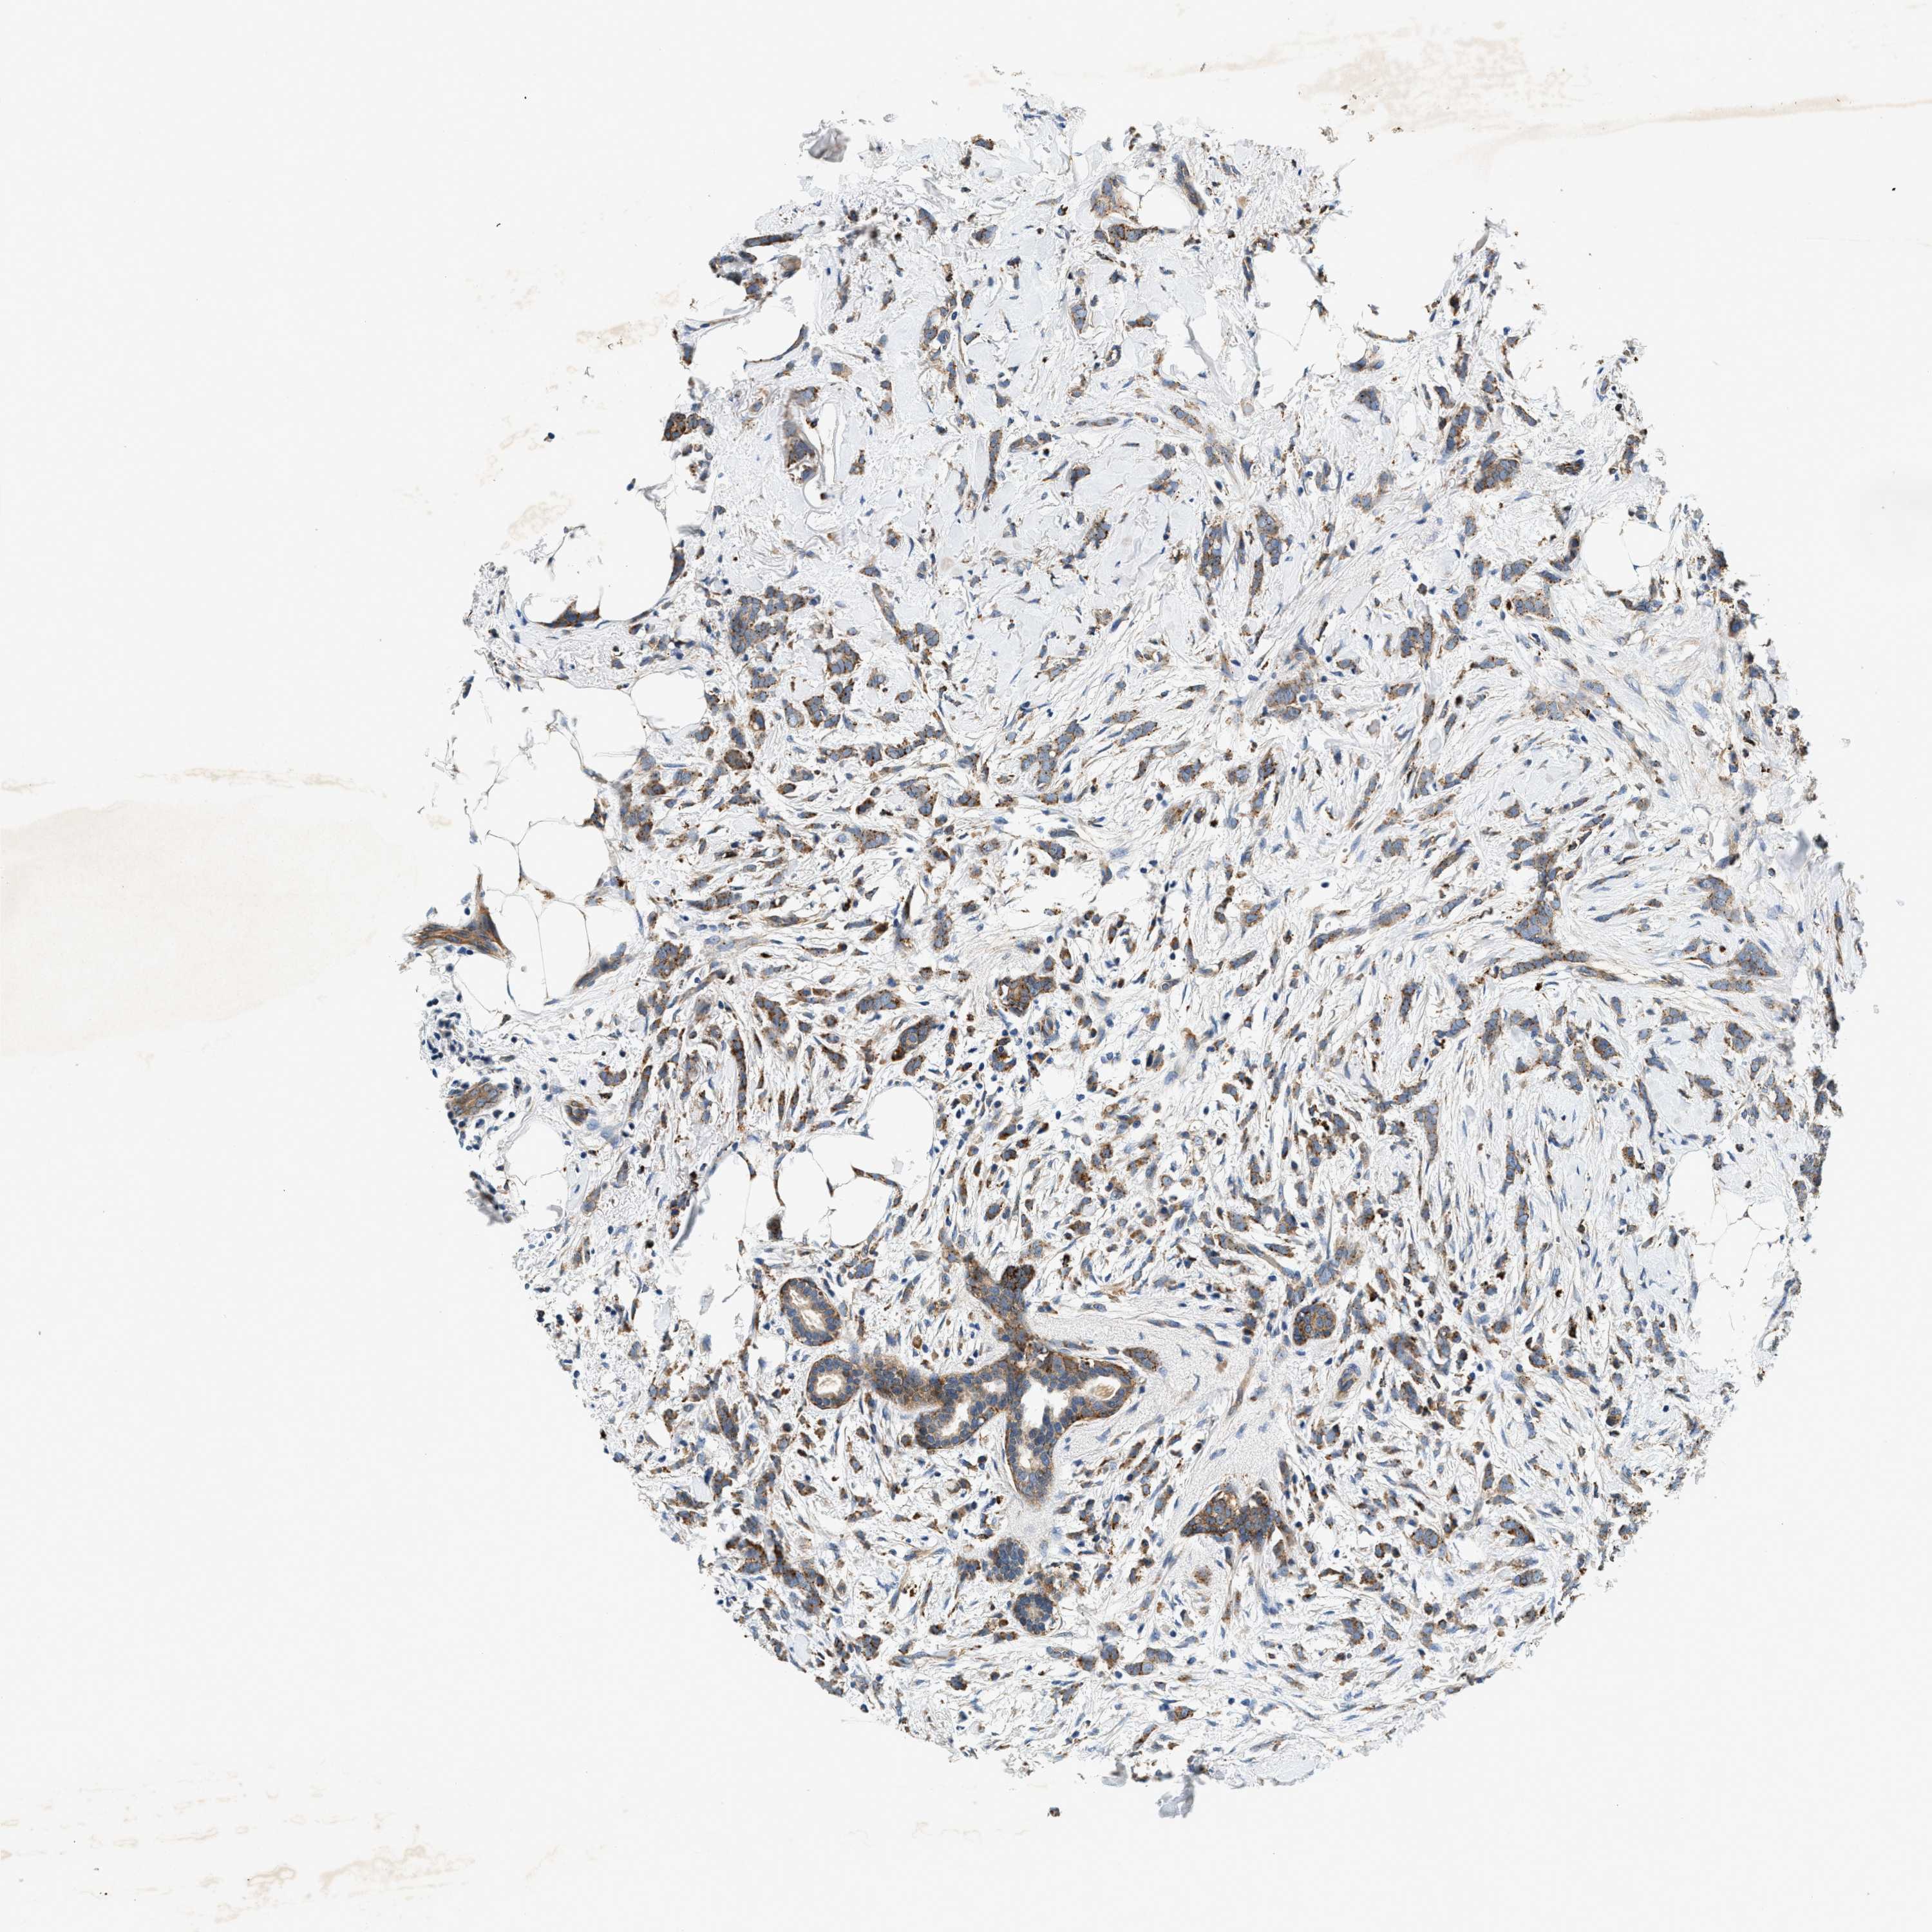

CANCER BREAST CANCER Show tissue menu

BRCA TCGA BRCA VALIDATION PROTEIN EXPRESSION